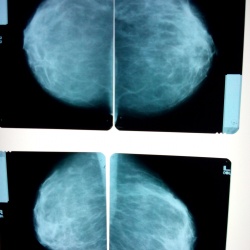

Смущает верхний квадрант левой молочной железы

Фкм?42 года на 7 день цикла.Прошу поделиться мнениями,заранее извините за снимки-учимся(маммограф "viola")-снимал на планшет.